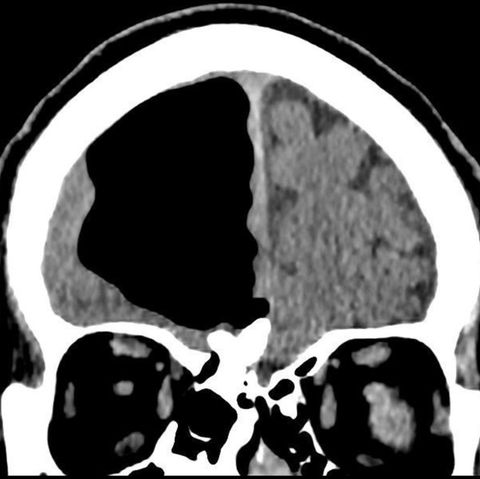

Die Nase lief und lief währenddessen unentwegt weiter. Die Ärzte verschrieben ihr allerlei Medikamente. Nichts wollte helfen. Sie wurde mit Verdacht auf eine Allergie etliche Male nach Hause geschickt. Bis vor ein paar Monaten. Zu diesem Zeitpunkt kämpfte Jackson mit ihrem Schnupfen bereits zwei Jahre. Die erschreckende und auch irgendwie erlösende Diagnose: Es handelte sich keinesfalls um Schnupfen, sondern um "Hirnwasser", in der Fachsprache nennt man es auch Liquor cerebrospinalis (CSF). Das "Hirnwasser" tropfte durch ein kleines Loch im Schädel der Amerikanerin.

Morgens wachte Jackson häufig auf und die komplette Vorderseite ihres T-Shirts war durchnässt. Nach eigenen Angaben verlor sie durch ihre Nase jeden Tag bis zu einem halben Liter Flüssigkeit. Das "Hirnwasser" ist farblos und klar und schützt das Gehirn und das Rückenmark. Dass die Flüssigkeit aus dem Hirn tropft, ist sehr selten. Fünf von 100.000 Patienten seien pro Jahr weltweit davon betroffen.

So wie Kendra Jackson. Wie "CNN" berichtet, gehen die Ärzte davon aus, dass ihr Autounfall Schuld an dem kleinen Loch in ihrer Schädeldecke hat. Die Symptome zeigten sich erst Jahre nach ihrem Unfall. Die Ärzte vermuten, dass sie sich vom Aufprall ein Schädel-Hirn-Trauma zuzog und sich Druck im Gehirn aufgebaut hat, sodass Flüssigkeit durch das Loch in der Schädeldecke entweichen musste.